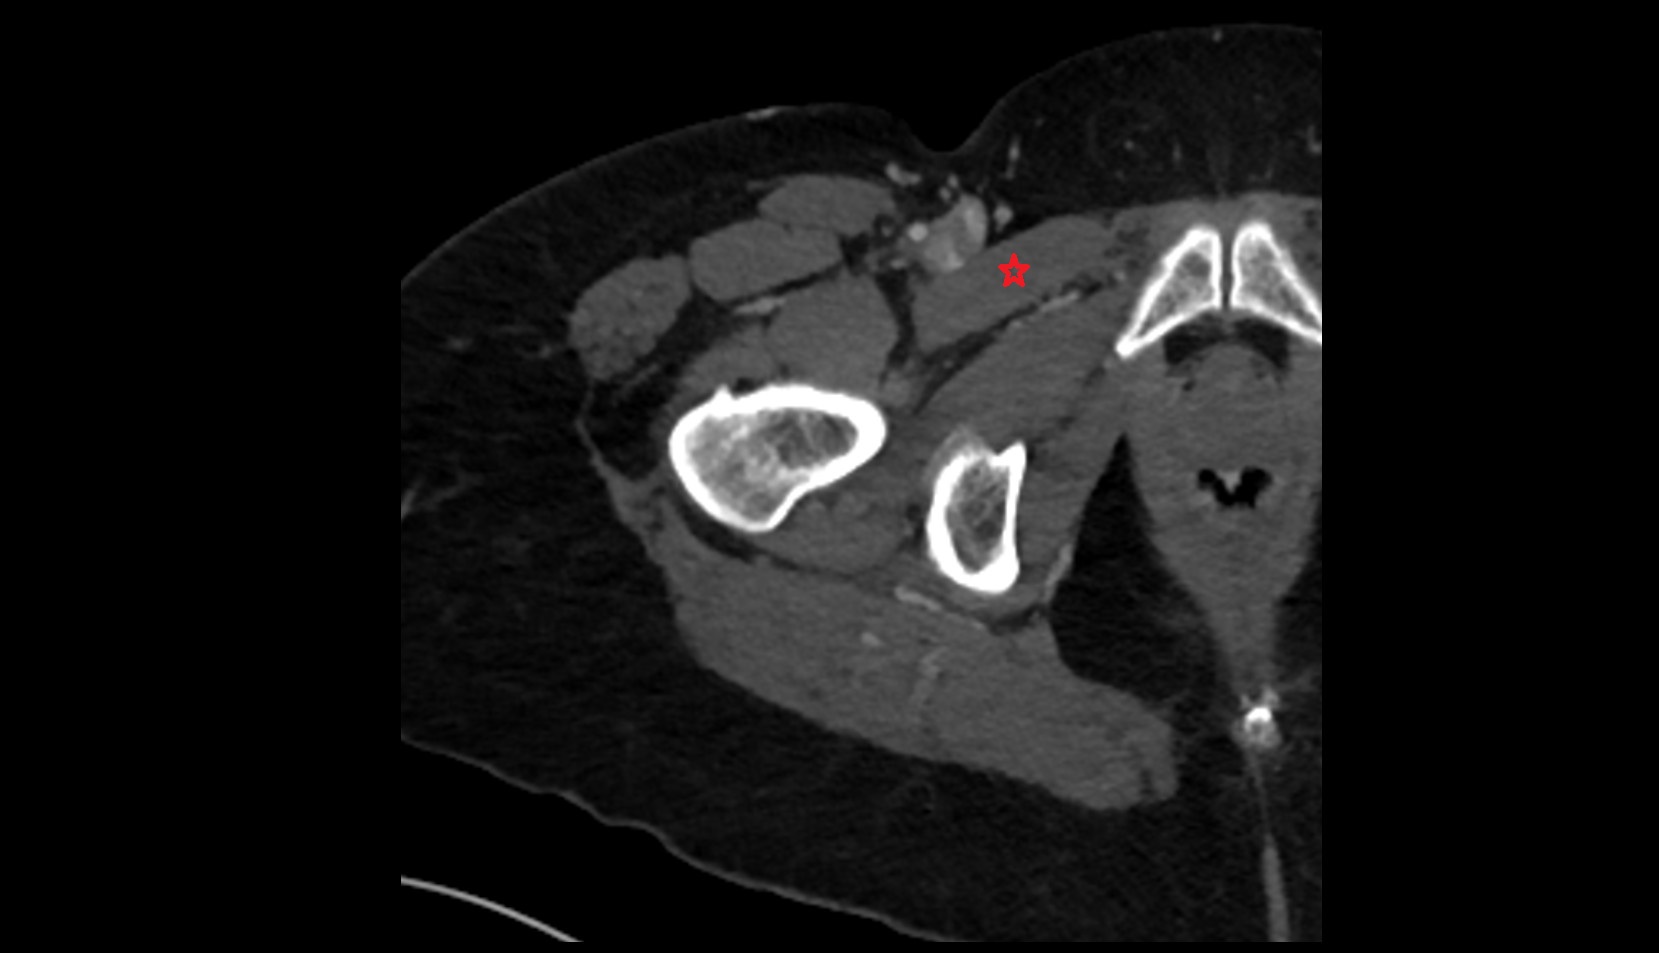

- External iliac artery

- Femoral artery

- Internal iliac artery

- Sciatic nerve

- Obturator nerve